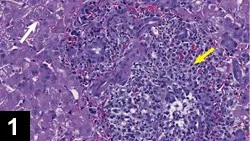

Figure 1. A granulomatous lesion from the liver. Typical liver cells are seen on the left (white arrow). Significant pyogranulomatous inflammation is visualized in the center and to the right of center (yellow arrow; magnification 20×). Courtesy Drs. Dave Getzy & Jeremy Johnson, IDEXX Laboratories

• Antibodies are attracted to the virus, complement is fixed, neutrophils and macrophages concentrate at the site, and granulomatous lesions develop (Figure 1).

• A lesion with perivascular granulomatous to pyogranulomatous inflammation and vasculitis is highly suggestive of FIP (Figure 1).10